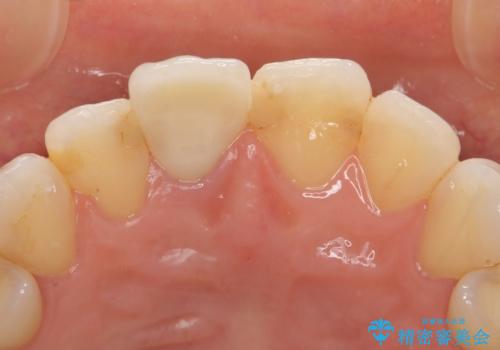

その後オールセラミッククラウン(スペシャル)による補綴を行いました。

前歯の補綴ではオールセラミッククラウンを希望される患者様が多いですが、オールセラミッククラウンの中でも、エコノミー、スタンダード、スペシャル、エクセレントとランクがあります。

その中でも特に審美性が高いのがスペシャル、エクセレントです。スペシャル、エクセレントは口腔内写真をもとに熟練の技工士が、患者様の口腔内に合わせたオーダーメイドのクラウンを製作致します。

今回用いたオールセラミッククラウンはジルコニアフレームという白い素材の上にセラミックを盛っているため、審美性が非常に高いのが特徴です。

また、ジルコニアは人工ダイヤモンドの材料にも使われているほど高い強度を持っており、そのためオールセラミッククラウンは審美性だけでなく、奥歯やブリッジの補綴も可能とするクラウンです。